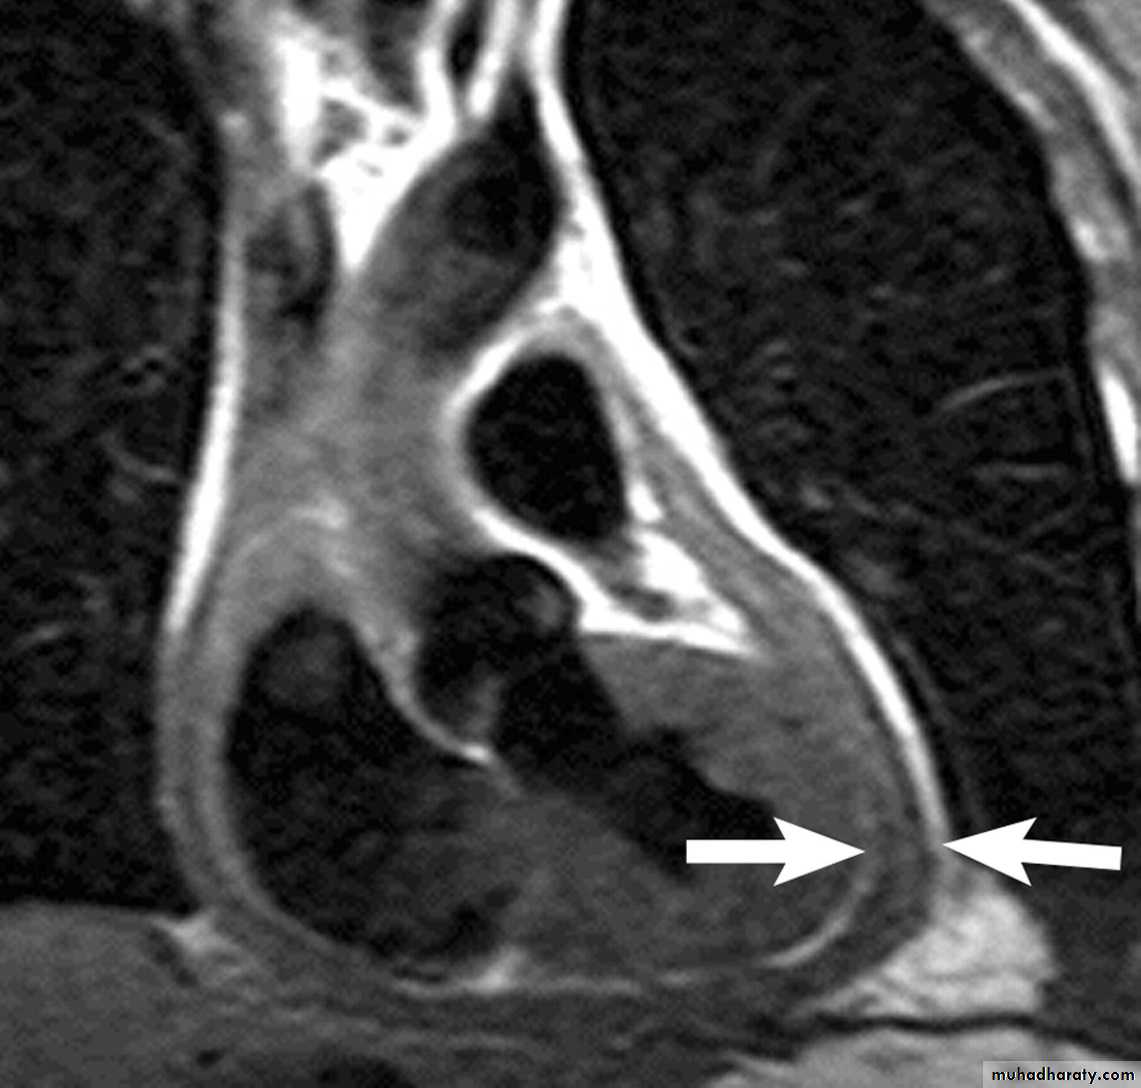

Investigations

Echocardiography & Doppler:RA & LA enlargement

Normal size ventricles

Pericardial thickening

CT/MRI: demonstrate the thickened pericardium